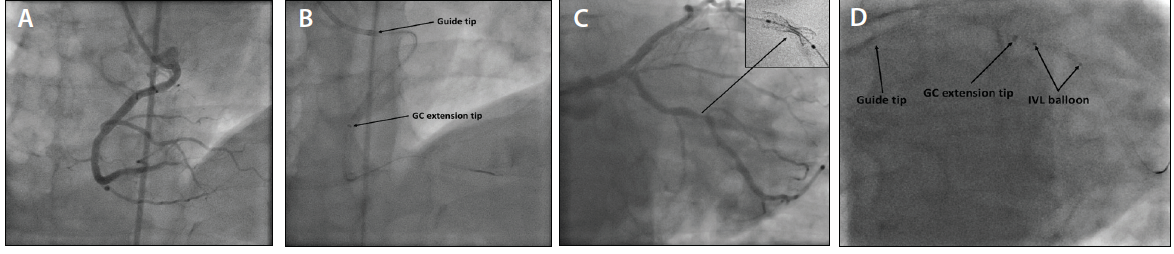

Depiction of guide extension catheter-facilitated tip-in technique. (A ...

The guide extension catheter is advanced towards the lesion more ...

Note the tip of the guide extension catheter (white arrow) very close ...